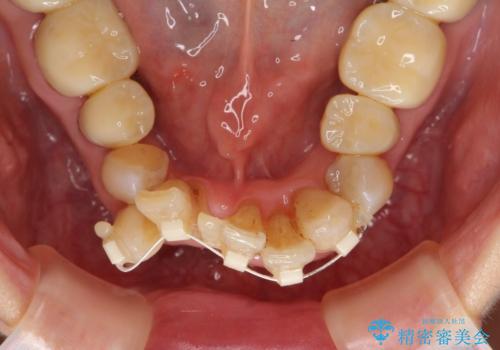

- 上顎前歯の黒ずみの改善、下顎前歯の十度なガタつき、矯正治療とセラミック治療を含む全体的な治療を希望され来院されました。

銀歯を高強度の仮歯に替えたのち、下顎前歯のみの部分矯正→全体的なマウスピース矯正治療(インビザライン)→最終的なセラミック治療と治療を進めます。